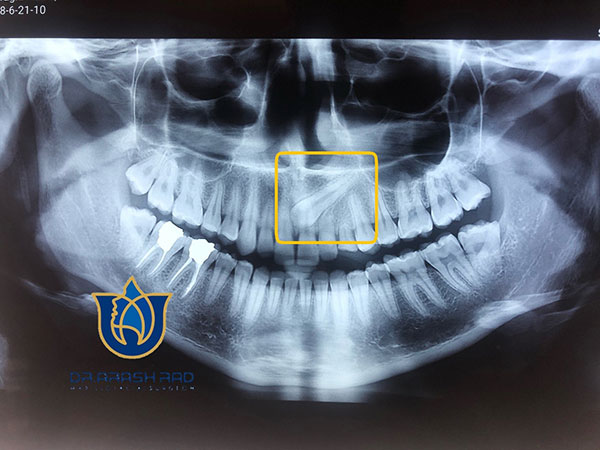

برای تشخیص نهفتگی دندان، متخصص شما را به انجام عکسبرداری و رادیوگرافی ارجاع می دهد. یک رادیوگرافی OPG حتما مورد نیاز است. در بعضی موارد برای تشخیص دقیق محل دندان نیاز به رادیوگرافی تکمیلی از جمله رادیوگرافی اکلوزال , لترال سفالومتری و یا CBCT می باشد.

نمونه ی رادیوگرافی OPG مربوط به دندان نیش نهفته:

اگر رادیوگرافی OPG تهیه کردید و با چنین تصویری مواجه شدید حتما از یک متخصص جراح فک و صورت کمک بگیرید.

نیش نهفته به علت اینکه در خلق و کف بینی قرار دارد در رادیوگرافی بطور واضح مشخص نیست.